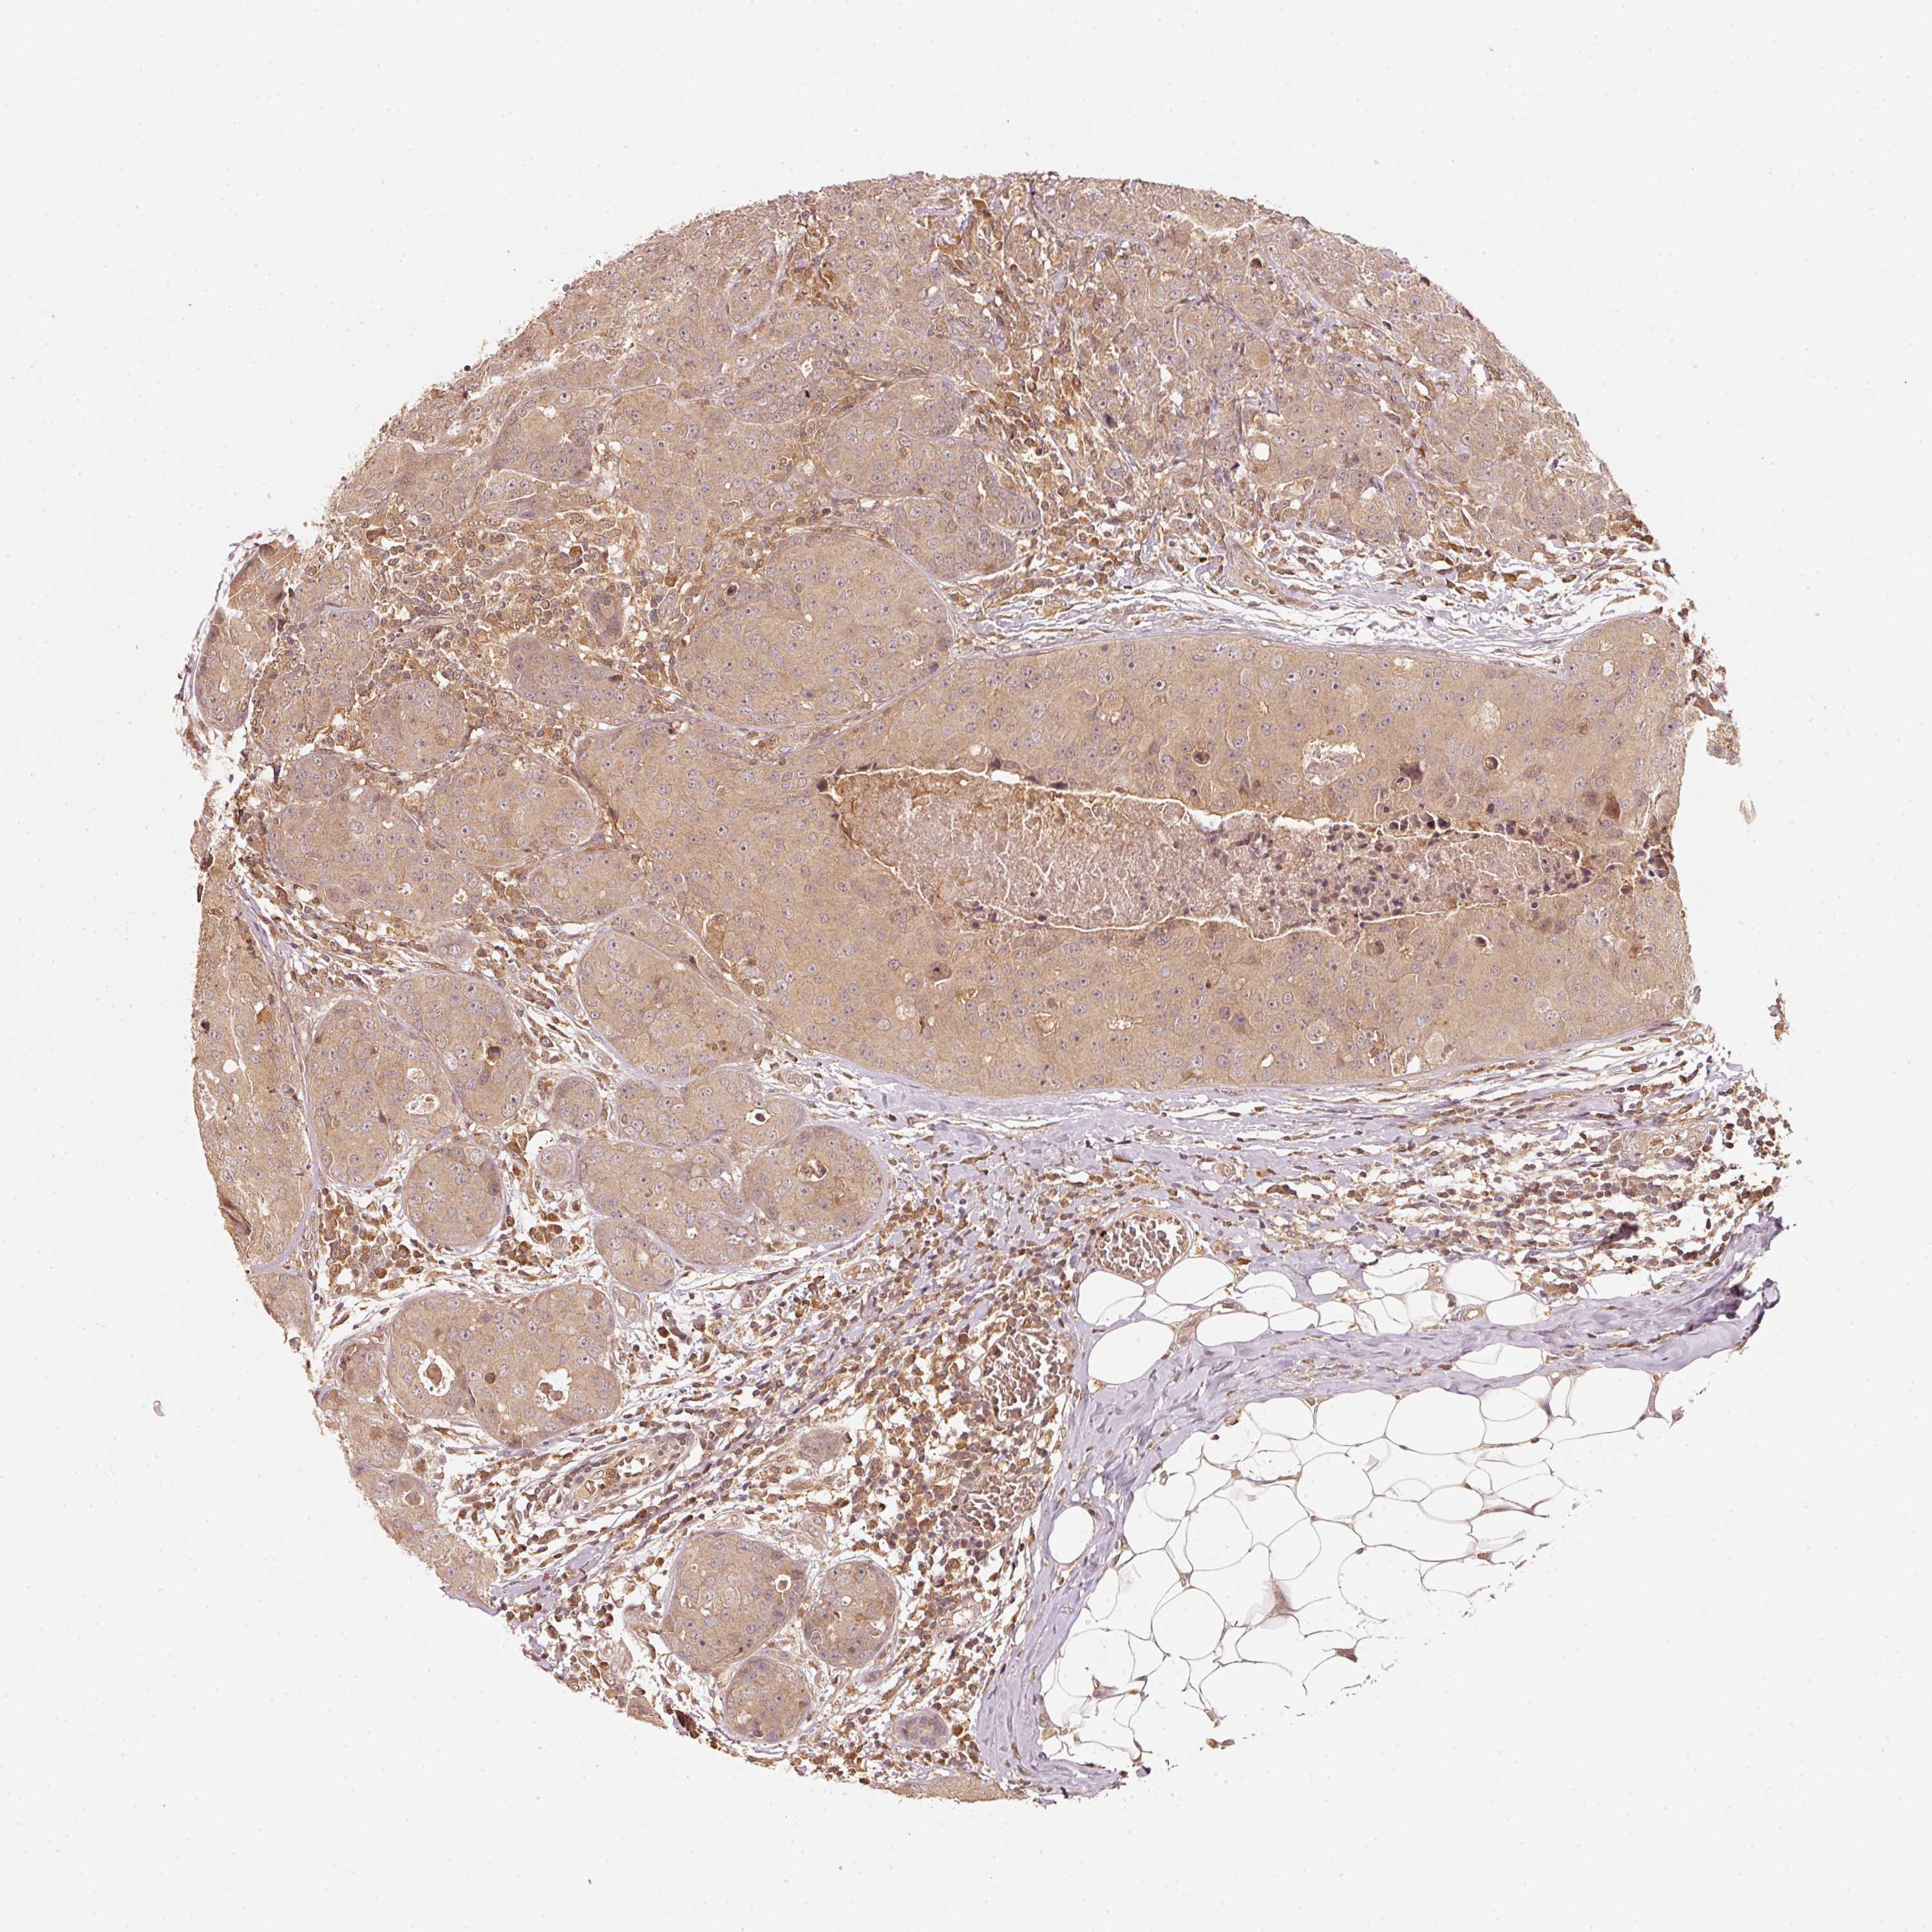

CANCER BREAST CANCER Show tissue menu

BRCA TCGA BRCA VALIDATION PROTEIN EXPRESSION

Breast cancer

Human cancer